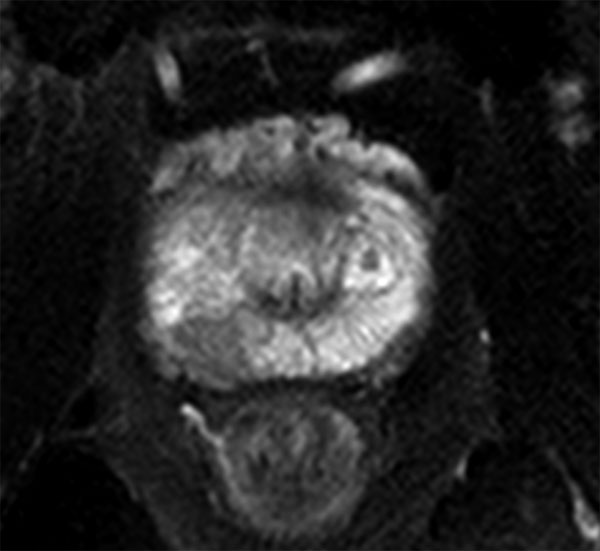

73 year old male with known prostate carcinoma. Size of 5mm, located in right posterior region. Patient is under active surveillance. Request for MR-guided prostate biopsy to re-evaluate.